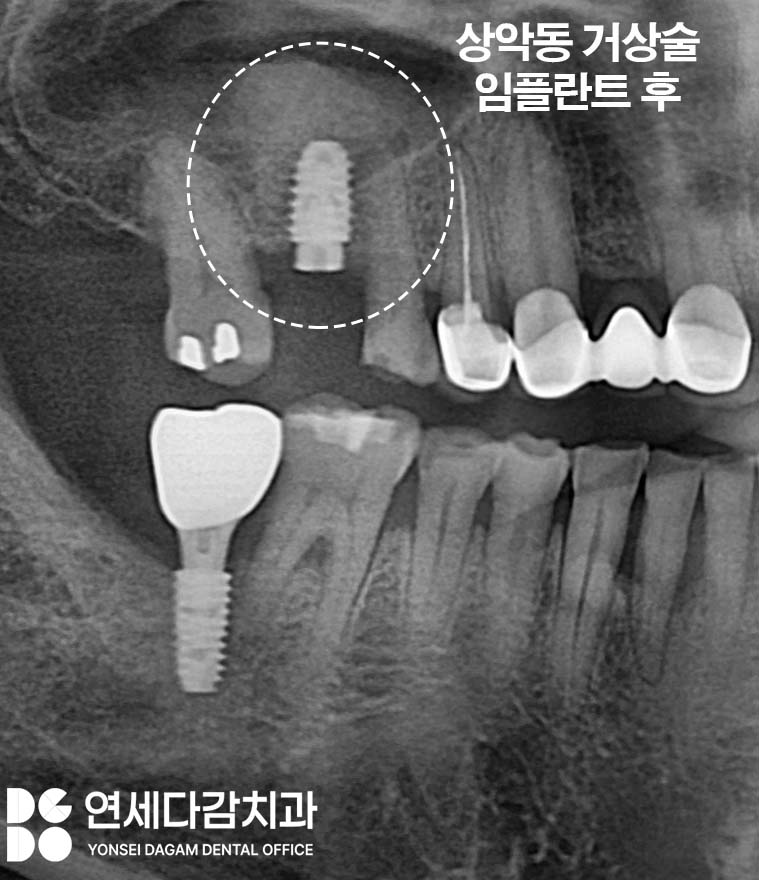

상악동 거상술을 시행합니다.

상악동 거상술이란

Maxillary Sinus Lift

상악동막을 위로 밀어올린 후

그 공간에 뼈이식재를 채워

임플란트를 심을 수 있는 높이를

인위적으로 만드는 방법입니다.

상악동 바닥을 밀어올리고

그 아래에 뼈를 채워서

임플란트가 들어갈 공간을 만드는 것입니다.